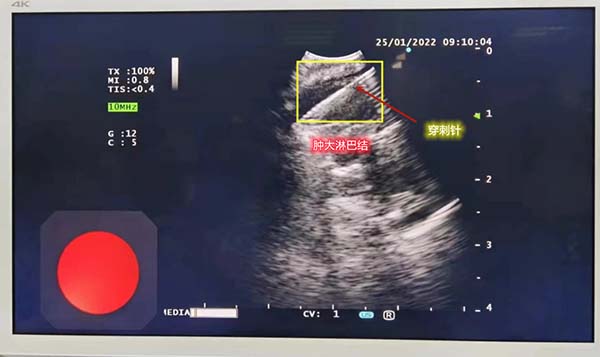

以往此类患者行穿刺活检均转诊到上级医院,给患者和家属带来不便。一直注重心胸外科领域发展的心胸外科主任周传江看在眼里、急在心上,在院领导的支持下,科室引进国内先进的奥林巴斯超声支气管镜。它是一种在支气管镜前端安装超声探头的设备,结合专用的吸引活检针,通过超声定位支气管外的病变具体位置,并在彩色多普勒的引导下避开血管,通过针吸和活检获得相应部位的细胞和组织,从而确诊疾病。

随后,心胸外科医护团队在麻醉科的支持下,成功开展超声支气管镜引导下纵隔淋巴结穿刺活检术,对无法通过普通气管镜检查取活检组织的患者,以及在CT引导下通过肺活检不能取得病理组织的患者,均在无痛超声气管镜的引导下实施支气管粘膜、隆突前间隙淋巴结针吸活检术,取得了良好标本进行病理学检查,最终明确肿块性质、病理分型及诊断,不仅减轻了患者的痛苦,更为下一步治疗提供了精准依据。术后患者说:“没想到只是睡了一觉,检查就做好了,一点也不痛苦。”

目前,心胸外科开展的超声内镜下纵隔淋巴结穿刺活检术,已成功实施30余例,标志着我院支气管镜下的诊断技术迈上新台阶,科室以精准的穿刺、安全的活检、良好的服务为肺与纵隔疾病患者带来新的福音。